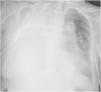

A 77-year-old woman was admitted to the hospital for bowel obstruction. A central line was placed in the right subclavian vein to initiate parenteral nutrition in the setting of a non-operative management strategy. On admission day 4, the patient developed acute respiratory failure, requiring ICU admission. Point-of-care pleural ultrasound revealed a complex, non-septated massive right pleural effusion with swirling, punctiform internal echoes (plankton sign) (Fig. 1, Video 1). A chest X-ray prior to drainage insertion confirmed the massive effusion (Fig. 2) and revealed displacement of the tip of the central line, compared to the immediate control after its insertion. A thoracostomy catheter was placed, demonstrating a milky-white output from the pleural space (Fig. 3), with high triglyceride (2503 mg/dL), low cholesterol (<20 mg/dL), and high glucose (682 mg/dL) levels, consistent with nutrithorax. Although uncommon, vascular trauma or direct leakage may cause nutrithorax that may be identified with ultrasound.